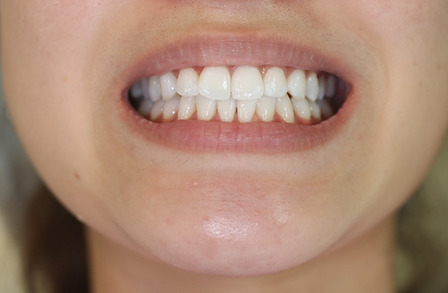

1矯正・マウスピース【治療例1】

治療前